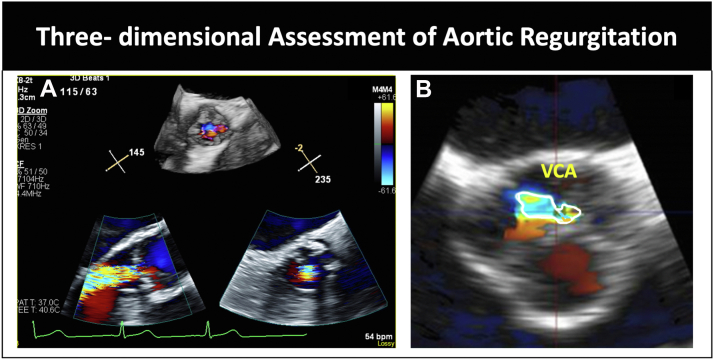

Figure 4.

(A) Three-dimensional assessment of aortic regurgitation. (B) Multiplanar alignment and measurement of 3-dimensional vena contracta area. VCA, vena contracta area.

There are potential limitations of some of these quantitative metrics because certain metrics (such as regurgitant jet width and ratio to left ventricular outflow tract [LVOT] diameter) assume a circular regurgitant orifice, which is often not the case in patients with BAV. Therefore, in patients with BAV, it is recommended to rely more on vena contracta width and the quantification of effective regurgitant orifice area and regurgitant volume using the proximal isovelocity surface area method (although this method can also have limitations in patients with eccentric regurgitant jets).